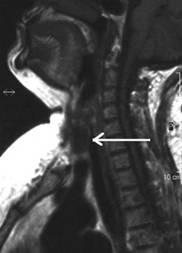

Aceeasi pacienta cu mica formatiune

nodulara medial de carotida dreapta - IRM

Aceeasi pacienta. IRM evidentiaza o formatiune neevidentiata ecografic, metastatica histologic.